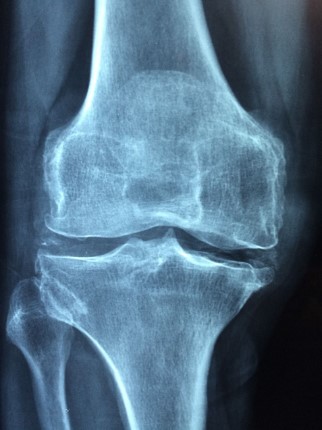

Nesta quinta-feira (20) é celebrado o Dia Mundial de Combate à Osteoporose, uma doença silenciosa no estágio inicial, onde há redução de massa óssea que causa o enfraquecimento dos ossos e, consequentemente, aumenta o risco de fraturas.

As áreas mais comuns de fratura são a coluna (vértebra) e o colo do fêmur, locais que mais sustentam o peso corporal.